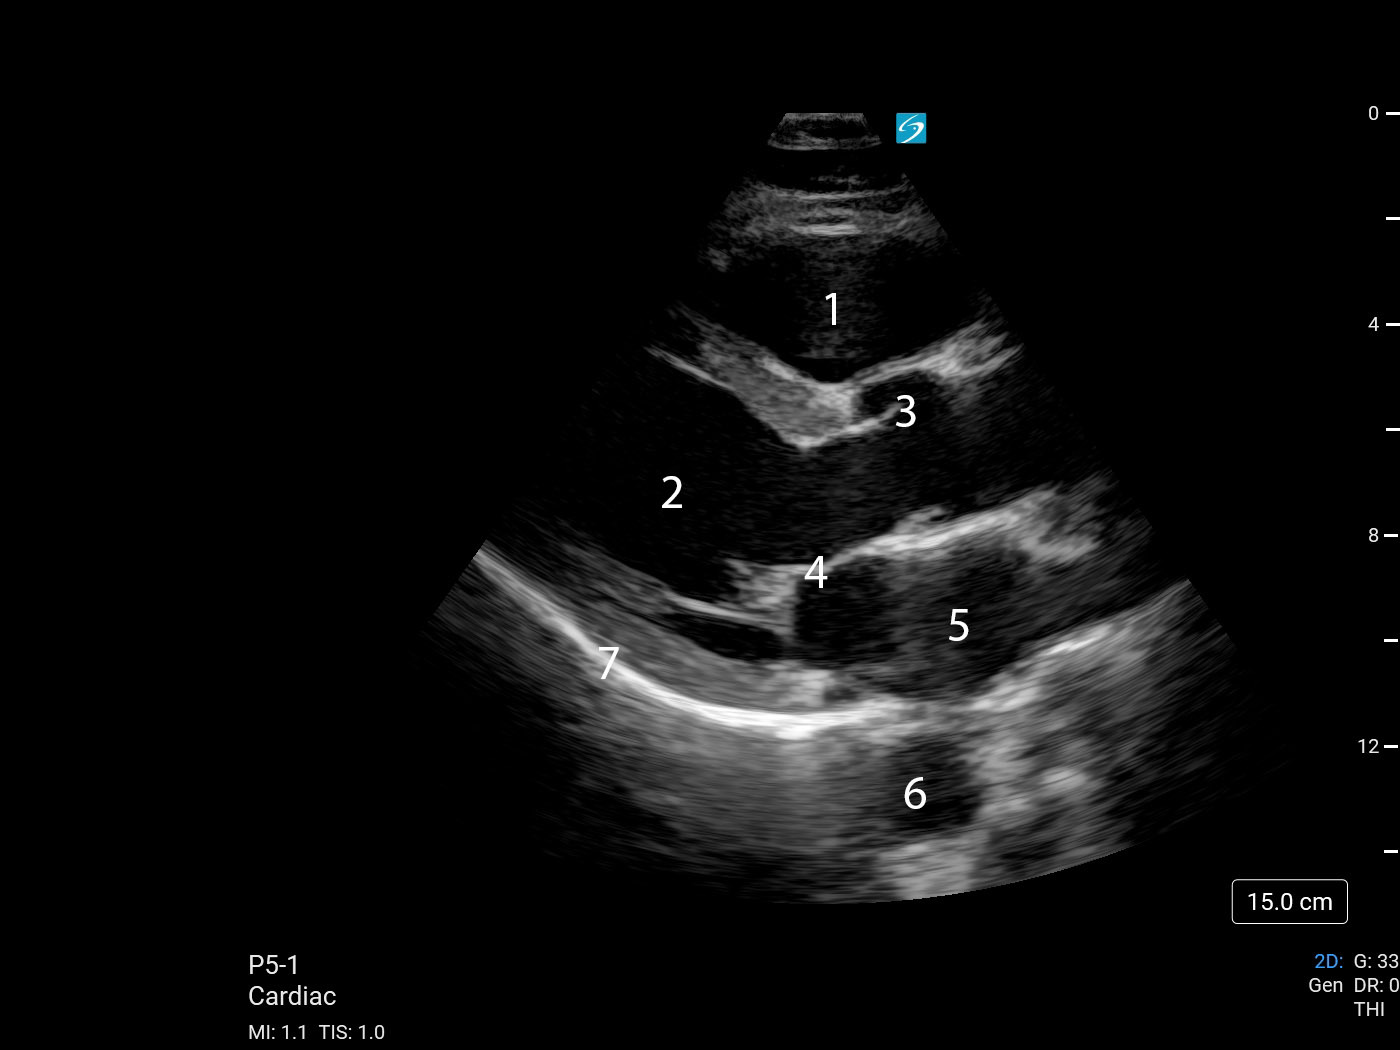

Heart Parasternal Long Axis (PLAX) (Sonosite PX P5-1) 2 Image

1. Right Ventricular Outflow Tract (RVOT)

2. Left Ventricle (LV)

3. Aortic Valve (AV)

4. Mitral Valve (MV)

5. Left Atrium (LA)

6. Descending Thoracic Aorta (DTA)

7. Pericardium